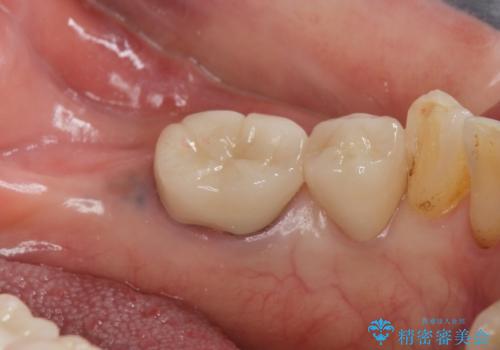

- 左下の大臼歯(6番)の根の治療を行いました。

その代わり、現在ある歯をしっかり治療することになり、左上下の治療を行っています。

左下6番の根管治療は六本木院の林院長にお願いしています。